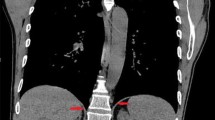

Mapping involves finding the motor point of the diaphragm where stimulation causes the greatest contraction of the diaphragm. The mapping instrument is held onto the diaphragm by suction with stimulation from a clinical station, and both qualitative and quantitative data is obtained from the stimulation (Fig. 1). Quantitatively, changes in abdominal pressures are measured from one of the laparoscopic ports. Qualitatively, visual observation of the diaphragm motion during a stimulated contraction is used to assess the optimal location for lead implantation. The stronger the stimulated contraction, the closer the mapping probe is to the motor point of the diaphragm. Two electrodes are implanted: one at a primary site and one at a secondary site to capture additional diaphragm movement. Electrodes are then implanted using the electrode implant instrument (Fig. 2). The needle at the end of the instrument is placed into the diaphragm muscle and on withdrawal the barb on the end of the electrode releases, allowing the exposed electrode to stay in the muscle. These electrodes along with an anode are tunneled to an appropriate spot on the chest or abdominal wall. If the patient has a cardiac pacemaker, it is simultaneously interrogated while the diaphragm is being paced, to confirm no device-to-device interactions. Testing is performed at nominal and most sensitive sensing settings for the cardiac pacemaker and in sensing modes supported by the cardiac pacemaker, e.g., unipolar and bipolar sensing. Chest X-ray is obtained to evaluate for the presence of a large capnothorax from the insufflated carbon dioxide that may have tracked from the abdominal cavity through the diaphragm. A small capnothorax resolves spontaneously while a larger one may need to be aspirated.

A total of 88 patients were implanted from March of 2000 until September of 2007 with 43 patients just in the first 9 months of 2007 alone. In 87 patients the diaphragm motor point was identified with subsequent implantation of the electrodes. The only failure was in the second SCI patient, who was brought to surgery and was implanted, but who was never able to have stimulated tidal volume. At surgery both diaphragms visually appeared denervated and on retrospective review of his phrenic nerve study, he was found to have a false-positive original test result. There were no diaphragm injuries, solid-organ injuries, bleeding, bowel injuries, conversion to open operations or lung injuries leading to pneumothoraxes. There were no electrode erosions to structures in the abdomen, no electrode migrations, and no late change in electrode impedance. No diaphragm electrodes have broken to date. There was one delayed suture granuloma causing an infection at the epigastric port site where the diaphragm electrodes were connected to separate electrodes that were subsequently tunneled through the skin. This was treated by externalizing the electrodes and the DPS system was still functional. The second set of connectors is no longer used as the electrodes implanted in the diaphragm are now the same ones tunneled to the exit site. There were two superficial wound infections along the tunneled wires, one in each group. In the SCI patient a chronic gastro-cutaneous fistula was closed during the DPS implantation and in the ALS patient a simultaneous gastrostomy was done, so both cases had contamination. With oral antibiotics and shortening and retermination of the tunneled electrodes, both infections resolved. No electrodes had to be removed or stopped functioning. Every patient as part of the study had intraoperative chest X-ray and in 21 out of 50 SCI patients (42%) air was observed above the diaphragm. This was only observed in five of the ALS patients (13%). This was classified as a capnothorax secondary to air tracking above the diaphragm. It was treated with either observation or simple aspiration. The capnothoraxes caused no hemodynamic or respiratory problems. Table 1 compares the tracked adverse events between the two groups of implanted patients.

There have been no lung injuries, but air has been identified above the diaphragm due to CO2 tracking from the pressurized abdomen to the pleural space. This has been described as a capnothorax and was prospectively tracked. In no case has the gas in the pleural space been from an injury to the lung itself. The latter would have been identified from having a continuing air leak from a chest tube or an increasing size pneumothorax after the laparoscopic procedure. All of the patients, by the nature of their tetraplegia, are on positive-pressure ventilation during and immediately after anesthesia, which would have potentially increased any air leaking from an iatrogenic lung injury. Capnothorax is therefore regarded differently from a pneumothorax related to lung injury.

During the course of this study, the phenomenon of gas tracking into the pleural space was also being described in other laparoscopic surgeries. Clements and colleagues [20] at Vanderbilt did chest X-rays on 45 patients undergoing laparoscopic foregut surgery that involved operations around the diaphragm and 21 (47%) had extra-abdominal gas identified. In another report extra-abdominal gas was identified in 85% of patients undergoing laparoscopic Nissen fundoplication when a more sensitive test, such as computed tomography (CT) scan, was performed after surgery [21]. Clements states that this air caused no clinically significant events that altered the course of the patients, and we found similar results in our tetraplegics undergoing diaphragm pacing, although a slightly different algorithm is used based on these patients. Patients undergoing laparoscopic foregut have both a normal inspiratory and expiratory system so that CO2 that has tracked to the chest space is rapidly absorbed. The lung can expand rapidly when the patients have a large inspiratory force during awakening from anesthesia and the collapsed airways can expand. Tetraplegics implanted with the DPS have no inspiratory or expiratory capabilities and are on set-volume ventilators. Their lungs therefore do not typically expand to fill this empty space. In the first patient in which this was seen, we placed a chest tube to re-expand the lung. This case prompted a change in the management of subsequent patients with capnothorax. We found that capnothorax may, in most cases, be observed and allowed to resolve expectantly in nontetraplegic patients. Due to the rare nature of ventilator-dependent tetraplegia and the fact that many patients utilized air travel to go to the implantation site, we did not want patients traveling with a nonsymptomatic but stable capnothorax. The present management of an observed capnothorax is to treat by initially giving much larger mechanical breaths via the patients’ tracheostomy and repeating the chest X-ray in the recovery room. If the capnothorax is still present, then it is aspirated by a method most familiar to the implanting surgeon (either a small pediatric chest tube or a thoracentesis needle).